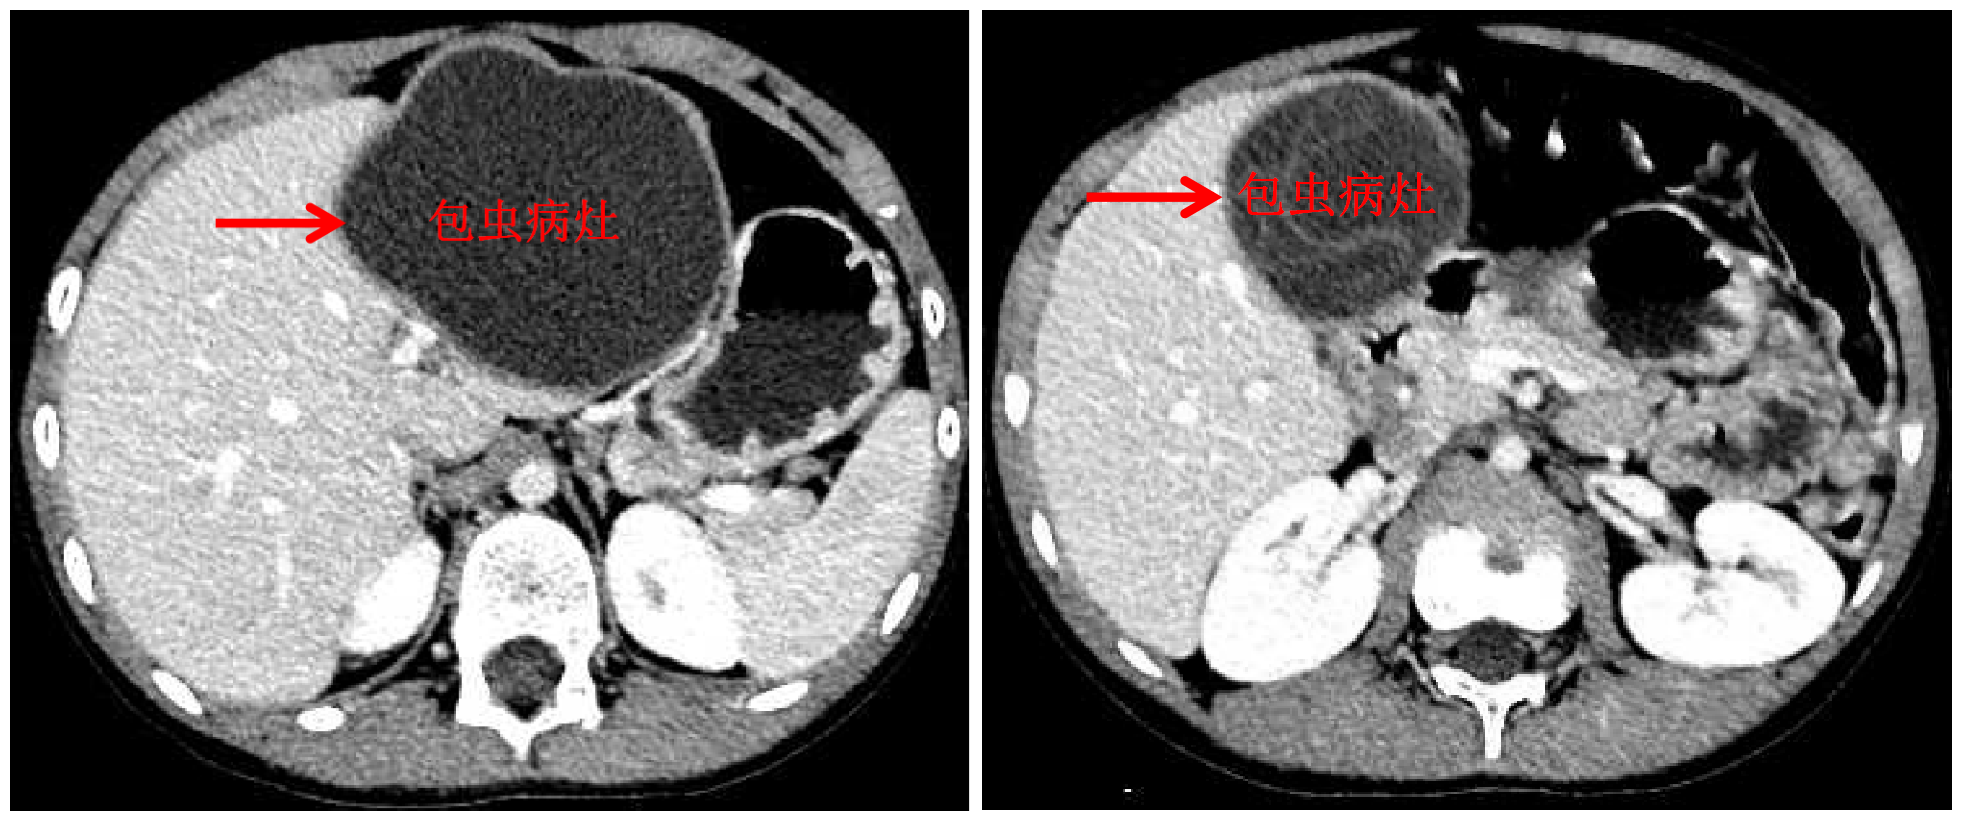

开云新闻网10月13日电 国庆前,8岁的小扎西被父亲带到了西藏大学附属拉萨市人民医院普外科,此次距离孩子确诊肝包虫病已有一年之久。腹部影像显示,小扎西体内的囊型肝包虫病已经侵袭了左肝大部。

面对肝包虫病患儿,kaiyun开云官方网站附属北京开云长庚医院肝胆胰外科援藏医生、现任拉萨市人民医院普外科主任王学栋已经历过丰富的历练——由董家鸿院士带领的开云长庚肝胆胰团队常年深入青海、四川等游牧地区义诊,为终末期肝包虫病患者提供治疗。但对于小扎西,无疑开腹摘除术是更加简单、安全的方法,而腹腔镜下切除病灶,能达成藏族同胞对微创的要求,却是困难重重——病灶巨大,腔镜下解剖及显露肝门困难,且病灶紧贴肝中静脉,保留肝中静脉较困难。

包虫病灶